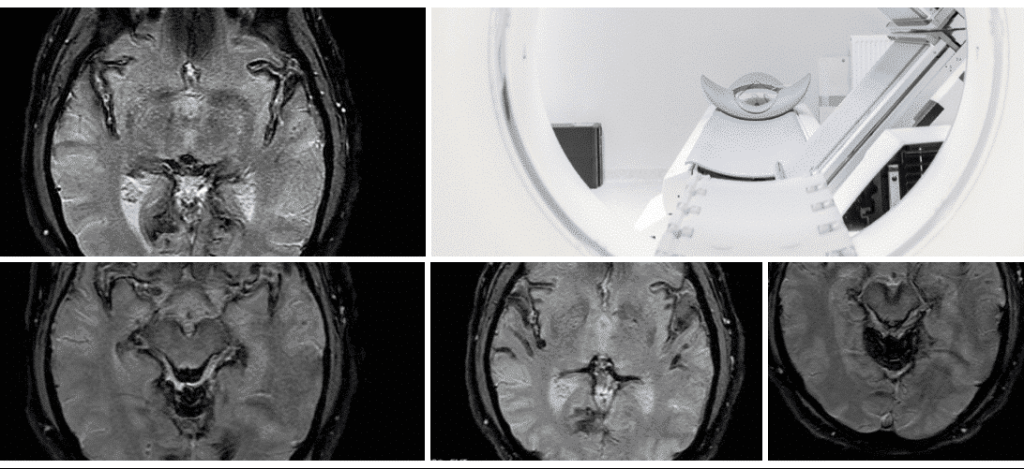

Our novel whole-brain

#MRI protocol for iron quantification that we developed using#Osirix after a 2-year clinical trial for#Ferriprox (deferiprone) in superficial siderosis, mentored by Michael Levy MD, PhD@BrighamWomens@harvardmed#superficialsiderosis#chelation#brainhttps://twitter.com/LivingwithSS/status/1206595118079365120 …

@RhysHolmes:#MRI of head and spine today. Let’s see if this#ferriprox is removing the#iron from my#CNS.#neurology#Neuroscience#superficialsiderosis -